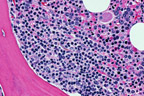

FCC lymphoma, mixed

Note the presence of both small-cleaved and large cells.

Follicular lymphomas are composed of malignant cells that resemble their equivalents in the normal lymphoid follicle. These cells include small-cleaved cells, large-cleaved cells, and large-non-cleaved cells, where "cleaved" refers to marked nuclear indentations or clefts. Generally these cells have little cytoplasm. The small cells ("centrocytes") tend to have dark, clumped chromatin and no or inconspicuous nucleoli. The larger cleaved or non-cleaved cells, sometimes called "centroblasts", have more open (clear) chromatin, typically with multiple prominent, bluish nucleoli that tend to cozy up to the nuclear membrane. In contrast, immunoblasts, which are less numerous in follicular lymphomas, have more abundant reddish-blue cytoplasm and prominent, central, reddish nucleoli.